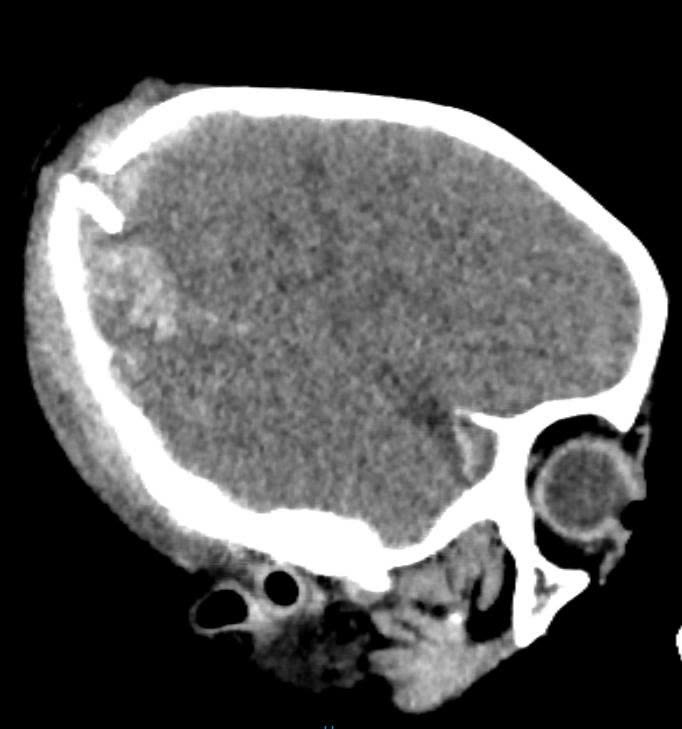

Hình ảnh chụp cắt lớp vi tính vùng đầu của bệnh nhi - Ảnh BVCC

Bệnh nhân được chỉ định chụp cắt lớp vi tính sọ não có kết quả: tụ máu dưới màng cứng bán cầu não phải, xuất huyết dưới nhện lan toả, dập não, vỡ xương thái dương và xương đỉnh hai bên, kèm theo mảnh xương rời trong hộp sọ.